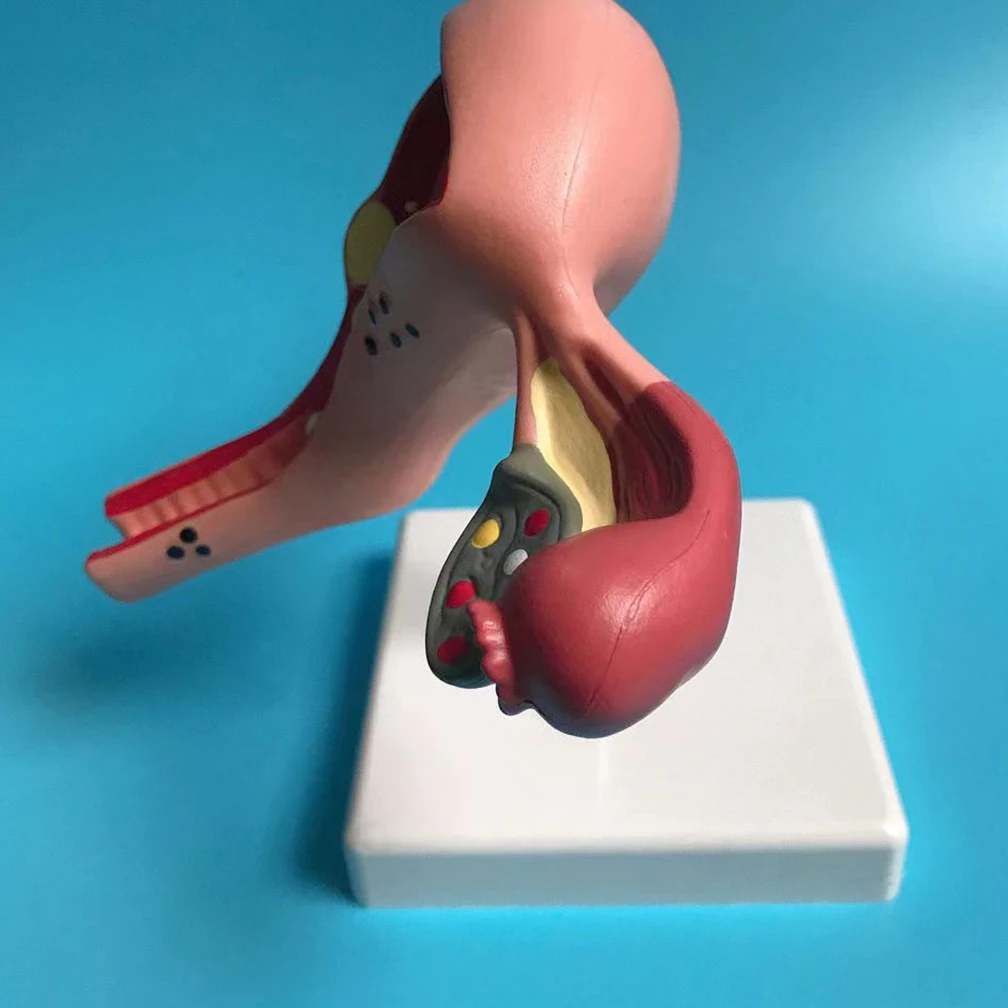

Анатомия женского организма: строение и функции матки

Раздел: Фотопуть к знанию